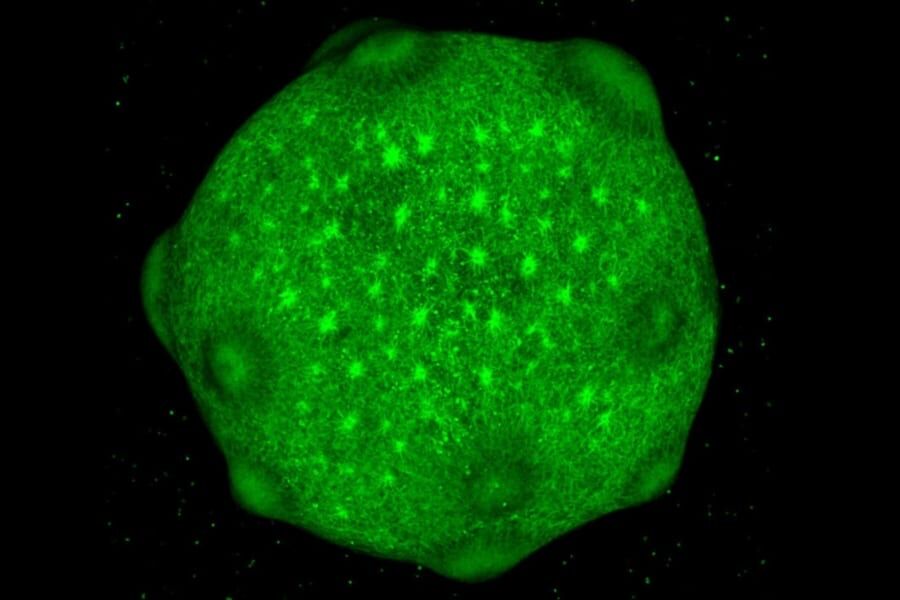

人工培養脳を「乳児の脳」まで生育することに成功

ヒトの脳を人工的に培養することが可能になってきました。

人工培養された脳は、一般に「脳オルガノイド」と呼ばれ、

長期培養された脳オルガノイドでは、

活性化している遺伝子が大きく変化し、

産後約300日目の乳児の脳と、

同じようなパターンに変化していたのです。

長期培養された脳オルガノイドが、

乳児の脳の代用品として使える可能性が示されました。

乳児の段階に達した脳は胎児の脳に比べて被検体として優秀であり、

創薬などの分野で、より本物の人間に近い実験素材として用いることが可能です。